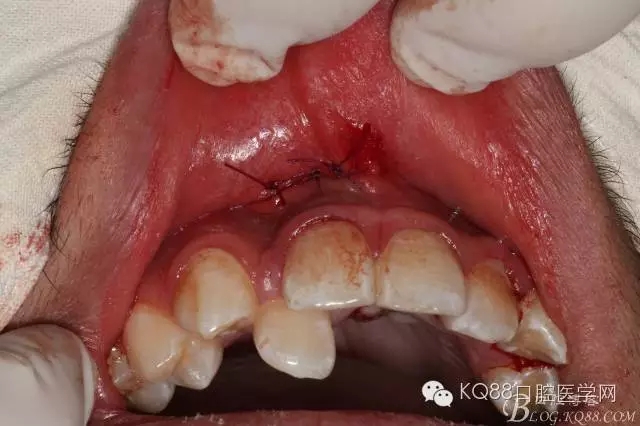

圖15.三針縫合拔牙創(chuàng)口

圖16.術(shù)后一周拆線時(shí)的情況:患者自述術(shù)后無腫脹、僅有輕微疼痛

圖17.術(shù)后拆線后的情況,創(chuàng)口輕度紅腫、囑咐患者注意口腔衛(wèi)生。兩周后行正畸治療